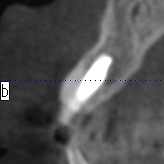

インプラント時のCTになります

骨幅もあり、埋入しやすかったです